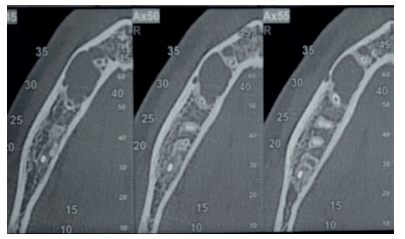

Se solicitó como prueba complementaria un CBCT mandibular. En los cortes panorámico, axiales y ortorradiales, se corroboró la presencia de lesión radiotransparente delimitada de contorno algo irregular y que no provocaba expansión de corticales (Figuras 1-4).

Radiográficamente presenta una imagen radiotransparente unilocular mostrando un festón en el área interradicular de los dientes afectos y de zonas edéntulas, pudiendo incluir sus raíces en la lesión, pero sin rizolisis; aunque en el sector anterior acostumbra a tener forma ovalada. Es radiotransparente con bordes irregulares, pero bien definidos. La expansión ósea sin perforación de corticales serían criterios asociados a esta lesión benigna, erosionando el endostio y por tanto adelgazando la cortical 2,3,5,6 .